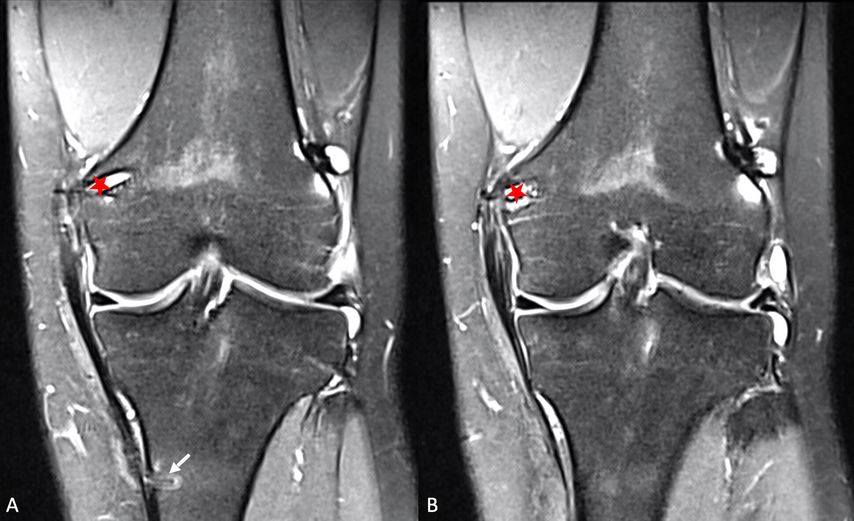

Abb. 10: MRT-Kontrolle 6 Monate postoperativ. A, B: 2 aufeinanderfolgende Schichten einer koronaren STIR-Sequenz einer eingeheilten sMCL-Rekonstruktion mit femoraler Schraubenfixation (roter Stern) und Fadenanker distal (Pfeil)